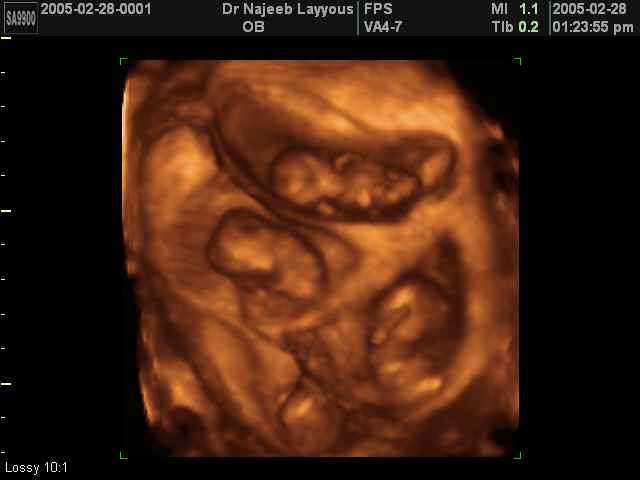

صور لتوائم بجهاز الالتراساوند ثلاثي الأبعاد | الدكتور نجيب ليوس

صور لتوائم بجهاز الموجات فوق صوتية ثلاثي الأبعاد